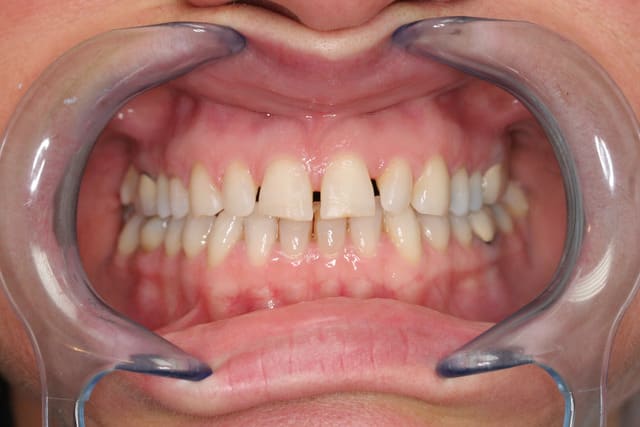

enfin un cas sympa pour faire des facettes, et a part une unitaire une fois c'est mon premier cas

le premier mock up était tout penché un peu plat, j'ai rajouté du composite par dessus la cire pour en faire un second qui nous plaise plus, à la patiente et à moi.

on a pas voulu toucher le collet de la 12, patiente pas motivée pour chir et ça me simplifiait la vie pour une première

ce sont des emax qui sont prévues